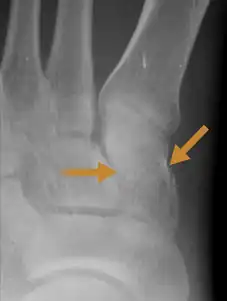

| An X-ray of a Medial cuneiform fracture | |